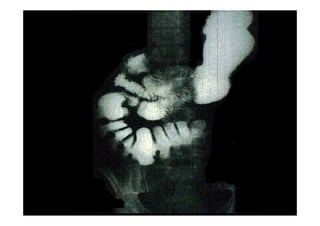

Corte de intestino grosso corado por Goldner

As fibras colágenas da submucosa estão em verde

http://www.ufrgs.br